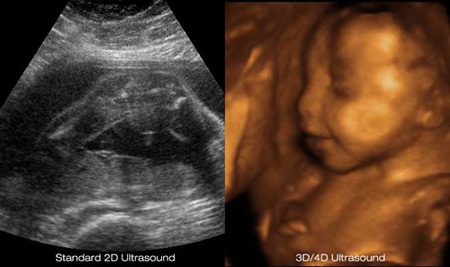

3D/4D Ultrasounds - Mother Nurture Ultrasound

www.mothernurtureultrasound.comultrasound 4d 3d hd 2d ultrasounds baby types animated gender technology mother packages gif imaging live difference clearview nurture check

www.mothernurtureultrasound.comultrasound 4d 3d hd 2d ultrasounds baby types animated gender technology mother packages gif imaging live difference clearview nurture check

Information Of Pregnancy Ultrasound Week-by-Week

my-fashion-school.blogspot.comultrasound information pregnancy abortion law texas before pregnant week 3d important 4d

my-fashion-school.blogspot.comultrasound information pregnancy abortion law texas before pregnant week 3d important 4d

jeminileywhenilookatyou.blogspot.comBest time to do 3d ultrasound during pregnancy. Pregnancy week 26. Prenatal ultrasounds

jeminileywhenilookatyou.blogspot.comBest time to do 3d ultrasound during pregnancy. Pregnancy week 26. Prenatal ultrasounds